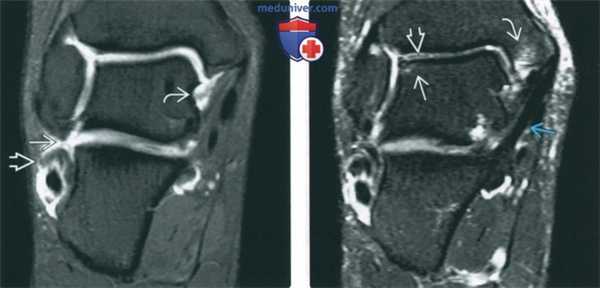

(Слева) МР-артрография в режиме Т1ВИ FS, первый из шести коронарных срезов, наглядно отражающий обширность повреждения медиальных и латеральных структур сустава при хронической нестабильности: определяется разрыв пяточно-малоберцовой связки и глубокого слоя дельтовидной связки. Короткая малоберцовая мышца расщеплена.

(Справа) МР-артрография в режиме Т2ВИ FS, коронарный срез: отмечается субхондральный отек таранной кости под нестабильным хрящевым фрагментом, а также отек костного мозга медиальной лодыжки. Большеберцово-пяточный пучок поверхностного слоя дельтовидной связки не изменен.